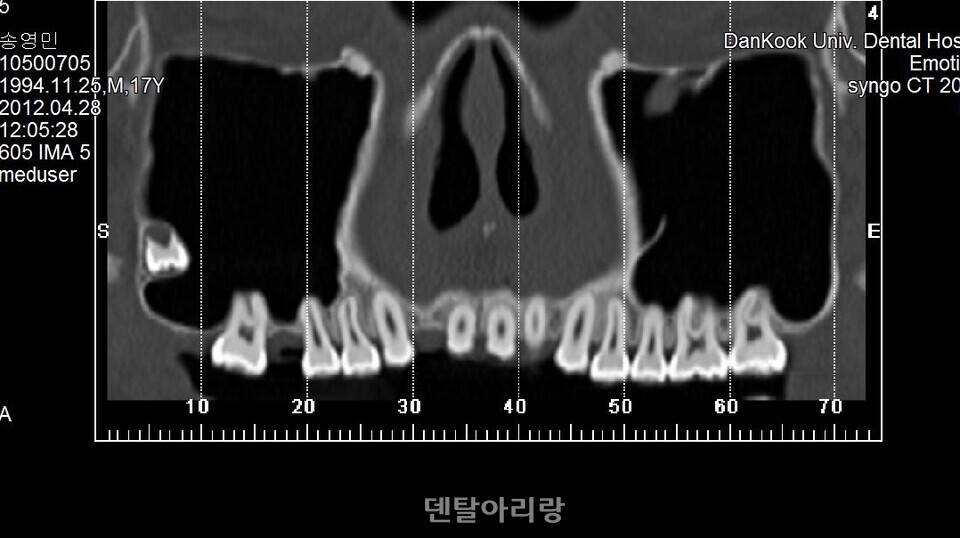

해부학적으로 상악동 외측벽 골내 동맥은 치조정(alveolar crest)으로부터 평균 약 16mm±3.5mm 상방에서 주행한다고 알려져 있으므로 골창의 상방 골삭제 선이 이 부위보다 하방에 위치하도록 디자인을 설정해야 한다. 상악동 골이식을 위한치조정 접근법은 상대적으로 측벽 접근 방법에 비해 상대적으로 출혈 등 합병증 발생이 적다고 할 수 있으나, 전혀 예기치 못하게 출혈이 간혹 발생하므로 주의가 필요하다. 치조종 접근법 후, 발생하는 출혈은 대부분 상악동 아래 바닥을 주행하는 상악 후상치조 동맥(posterior superior alveolar artery)의 손상과 관련이 있다<그림 13>.

△그림 13. 치조정 접근법에 의한 임플란트 식립 후, 상악동내 출혈

이런 경우, 구강 내로는 출혈이 없이 상악동과 상악동을 통해 비강으로 연결되는 매우 심각한 비출혈이 일어나며, 지혈이 어렵기 때문에 대부분 응급 상황으로 이어지게 된다. 따라서, 치조정 접근법을 통해 임플란트 식립 후, 구강내 출혈이 없더라도 환자가 수술 직후, 또는 귀가 후에 다량의 비출혈 증상을 호소하면 응급실을 통한 구강악안면외과 전문의에게 즉시 의뢰하여야 한다.